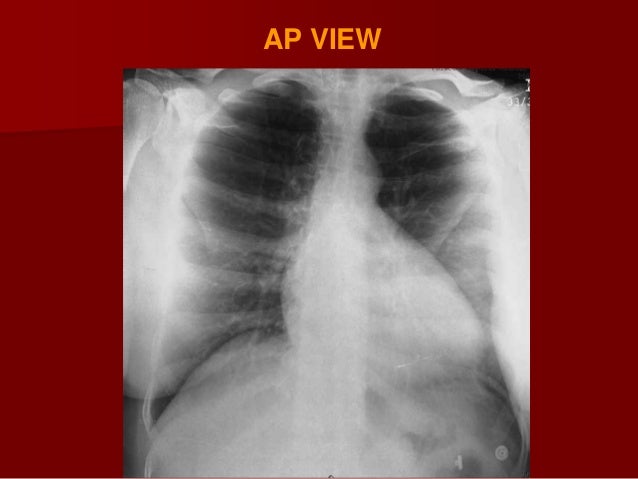

Ap vs pa view. Abc news is your trusted source on political news stories and videos. Note the ap sitting label. It is utilized in many imaging contexts including trauma postoperatively and for chronic conditions. The pa posterioranterior film is obtained with the patient facing the cassette and the x ray tube 6 feet away.

The image has been acquired by a mobile x ray unit in the resuscitation room. There appears to be a bilateral interstitial infiltrate also due to underinflation. The superior mediastinum appears widened due to ap magnification. This distance diminishes the effect of beam divergence and magnification of structures closer to the x ray tube.

Usually bedridden and infants. In simple words during the procedure of taking x ray radiograph when x ray passes from posterior of body to anterior it is called pa view. Ap erect view chest supine view 10. Ap kevin harvick was a sure bet to make the nascar finale and likely close out one of the most dominant seasons of the decade.

Ap projection images are of lower quality than pa images. Compare this image with the pa view below. Ap projection example. Clavicle remains at top of lung field 2.

The heart appears enlarged a combination of ap magnification and underinflation. Heart shadow looks larger 5. Like all methods of radiography chest radiography employs ionizing radiation in the form of x rays to generate images of the chest. A chest radiograph called a chest x ray cxr or chest film is a projection radiograph of the chest used to diagnose conditions affecting the chest its contents and nearby structures.